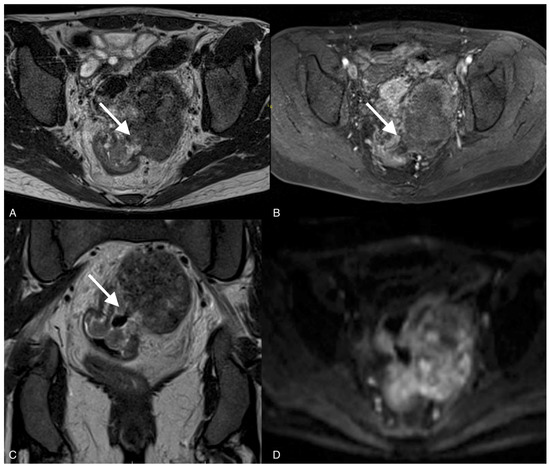

Figure 1.

Images from 58-year-old patient with carcinosarcoma of the ovary and recurrence in the rare form of giant cell carcinoma. The fistula between tumor and rectum (arrow), CT post-contrast image in venous phase obtained in the axial plane, shows pelvic tumor and adjacent intestine, fatty tissue between the tumor and intestine vanished as indirect sign of the fistula.

The median diameter of the relapsed tumor was 89 mm (range 36–130 mm). In all cases, fistulas formed between the tumor and large bowel. In three cases, fistulas formed between the rectum, including two between the sigmoid colon, one sigmoid and descending colon, one between the cecum and ascending colon, and one between the sigmoid colon and left ureter. On CT, in all cases, the fistulas were not directly visible, with only indirect signs of the fistula observed, such as infiltration of the intestine by the tumor, which we observed as vanishing of the fatty tissue between the tumor and the description of the intestinal wall, disruption of the intestinal wall, or the presence of gas in the tumor. In five patients, we observed thickening of the intestinal wall associated with a fistula (Figure 1, Figure 2 and Figure 3).